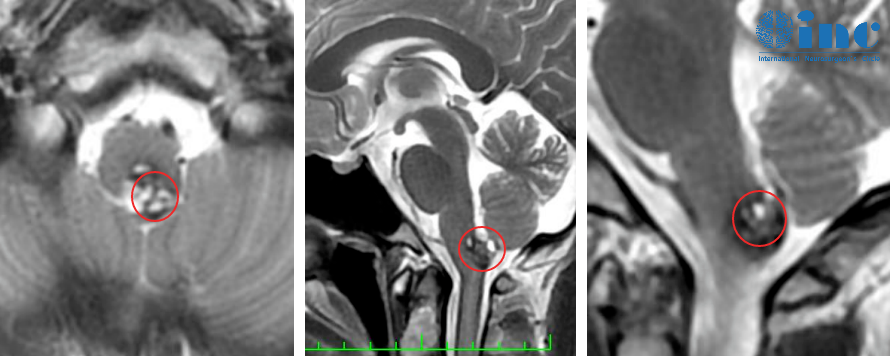

只要是睡眠质量不好,隔天的头就会不舒服,会疼会涨。同时这个难受的感觉会维持很长的时间,只有休息一会儿后,才会有所好转。这种症状持续了一个月,严重影响到阿朔的正常学习和生活,便在父母的陪同下前往当地医院行颅脑核磁检查,结果提示延髓异常信号,考虑海绵状血管瘤。

脑干是生命中枢,主管呼吸、心跳、意识、运动、感觉等,一旦在术中损伤,所造成的后果往往令患者及其家属难以接受;脑干仅拇指大小,神经核团集中,任何一个细微的操作偏差,都可能造成损伤。延髓位于脑干的下部,术中操作稍有不慎患者就可能出现心跳呼吸异常,术后无法自主呼吸、长期昏迷或植物状态需长期住ICU,甚至导致死亡,造成无可挽救的局面。

尽管患者目前的临床状况良好,但由于再次出血和产生更多神经功能障碍的风险,这位男孩的海绵状血管瘤有明确的手术指征。

是的,手术可以完全切除这个有潜在危险的海绵状血管瘤;患者越早接受手术,他要面临的出血或其他问题的风险就越低。因此,现在确实是手术的较佳时间。

对我来说,这并不是较复杂的手术。与其他手术相比,脑干的手术本身就相当复杂;与其他脑干海绵状血管瘤的手术相比,这个手术属于中等难度。对我来说,这种手术是相当切实可行的。在以前的类似病例当中,我的患者并没有出现过新发长期性神经功能障碍。病人在术后可能会出现轻度的短暂性感觉障碍,如果出现的话,风险低于3-4%。如果出现这种症状,肯定会在接下来的几周内恢复。术后不需要任何其他的治疗。我预期术后不会出现长期性的后遗症。